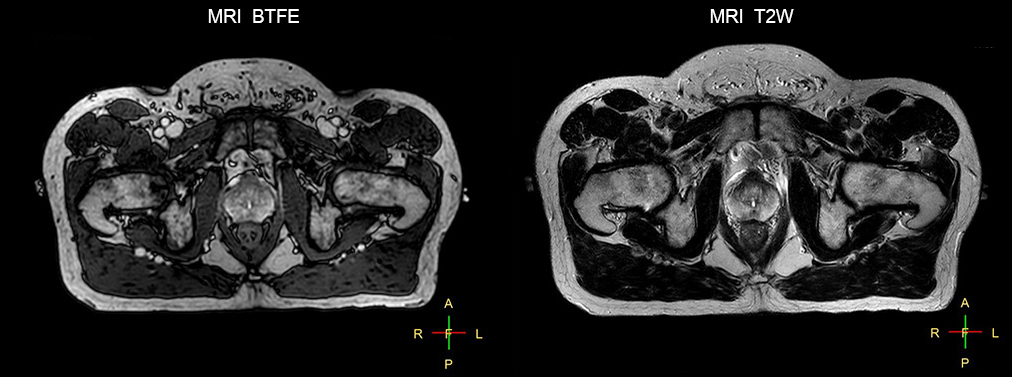

Impressive clinical benefits for prostate

“The biggest problem for CT-based planning, especially in prostate, is you can’t see the cancer very well,” says Dr. Stevens. “On CT it can be quite challenging to see the edge of the prostate especially at the apex. When the edge of the prostate can’t be delineated well on CT, radiation oncologists will increase their margins a little bit so they don’t miss it, but that can also increase toxicity.”

“Using MR, the prostate is well delineated. We quickly see the edges of cancerous tumors like in prostate cancer, and as normal structures can be defined, we can optimize the treatment plan to protect these organs and their normal function. This can potentially improve the outcome. And it improves workflow as well. We can contour more quickly, confident that the tumor is going to be in the field.”